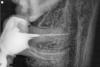

злата Опубликовано 21 февраля, 2009 Автор Поделиться Опубликовано 21 февраля, 2009 вот снимки,и много вопросов.Почему до сих пор болит зуб(7) с вкладкой при надавливании и накусывании.Коронки поставили а толку нет,жевать все равно не могу,больно.Очень ли проблематично будет удалить 8ку, и стоит это делать,пока зуб не тревожит Ссылка на комментарий

Bier Опубликовано 21 февраля, 2009 Поделиться Опубликовано 21 февраля, 2009 каналы недопломбированы, вкладка ужасная, кариес корня и неудаленная 8ка.... проблем достаточно. Ссылка на комментарий

Рина Опубликовано 21 февраля, 2009 Поделиться Опубликовано 21 февраля, 2009 У меня даже сердце прихватило,столько всего и сразу...а что с этим делать,как лечат кариес корня,чем грозит эта ужасная вкладка,мост стоит пока временно,есть ли возможность все исправить?Я так понимаю нужно менять доктора?????????? раз уж тут столько всего Злата, мостовидный протез необходимо снять. Нужно попытаться извлечь вкладку из корневого канала. Каналы необходимо перелечить, по снимку в одном канале материал выведен за верхушку корня (это тоже может вызывать болезненность при накусывании) в других -не до конца. Решить вопрос с зубом мудрости. По поводу кариеса корня сказать не могу, но прилегание вкладки к тканям корня - никакое. Да и длина корневой части вкладки должна быть не менее 1/2 длины корня. Но все будет зависеть от-того, удастся ли извлечь вкладку Ссылка на комментарий

Bier Опубликовано 21 февраля, 2009 Поделиться Опубликовано 21 февраля, 2009 такую вкладку как эта вполне реально вынуть имхо.перед протезированием необходимо удалить 8ку. Ссылка на комментарий

Андрей Опубликовано 21 февраля, 2009 Поделиться Опубликовано 21 февраля, 2009 Действительно, каналы надо переделать, в обоих зубах. Болит задний зуб моста? Там в задний корень не один, а два, второй не запломбирован, думую вкладка на станет превятствием к перелечиванию.Восьмерку Вам дернут в любом месте под местной анестезией.Удачи. Ссылка на комментарий